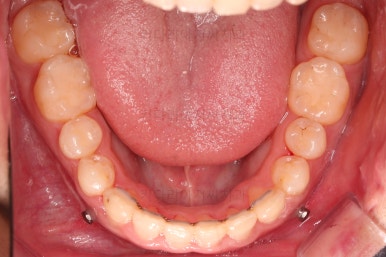

부산긴얼굴긴턱교정 전후 비교해 볼게요.

이렇게 비교해 놓으니 더 드라마틱하죠.

당연히 교합/위아래 폭 등 치열이 좋아졌고요.

얼굴 모습에서도 주걱턱이 개선되었고, 긴얼굴, 긴턱 등 길이 부분도 굉장히 좋아졌습니다.

적절한 협진을 통해서 과하지 않게 특유의 양악수술 느낌의 어색함 없이 개선이 잘 되었습니다.

얼굴 길이가 짧아지면 이렇게 훨씬 어려보이는 효과도 주게 됩니다.